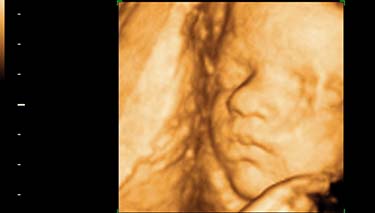

A 3D ultrasound takes thousand of pictures or photos of the baby at the once time. These are then translated by computer into 3 dimensional images which are almost as clear as a real life photograph. These still pictures of your baby mean that you can see your baby in three dimensions, rather than two.

There is a depth and shape to a 3D image, giving a clarity which is not as evident in a 2D ultrasound. This is because a 2D ultrasound sees through the baby to its internal organs and tissues. Whereas, with a 3D and 4D ultrasound the baby's skin can be seen so there is more of a realistic shape and form to the images. This is particularly clear when looking at the baby's face and delicate features.

Once these pictures are stored and shaded by the computer, they can be seen on the screen as clearer, 3 dimensional images. The width, height and depth of the baby and its internal organs can be seen very clearly. With 3D ultrasound the baby has a more realistic shape and form, with distinctly baby type features and look exactly as they would if they were already born, only smaller of course.

Parents need to rely less on their imagination with a 3D ultrasound. It's as if all the 2D images have been filled in and puffed out so the image is quite clearly a baby, rather than a grainy image on the screen.